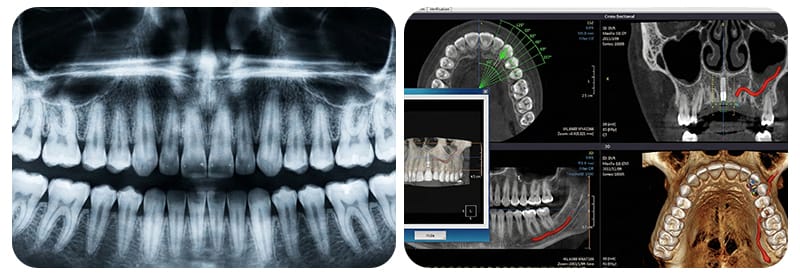

- 3D CT/CBCTのDICOMデータ原本(フォルダ一式) (CT DICOM for implant consultation)

- 何を確認するための資料ですか: インプラントを埋入する骨の形態を3次元的に確認します。

- 提出のヒント: 可能な限りDICOMデータの原本フォルダ全体が望ましいです。JPEGやスクリーンショットは断面の確認に限界があります。撮影した歯科医院・病院に「DICOMデータの原本提供」を依頼してみてください。

- パノラマ写真(2D)

- 何を確認するための資料ですか: 歯列全体と残存歯、大きな病変を広く見渡すスクリーニング地図です。

- 提出のヒント: 撮影画像とともに、撮影日を明記しておくと資料整理がスムーズになります。

- *パノラマ(2D)**は、一枚で全体を見渡す地図です。残存歯、大きな病変、全体の歯列を把握するのに有用です。ただし、深さの情報が制限されるため、神経管との距離、上顎洞との関係、骨幅などの3D的な判断が必要な状況では限界が生じることがあります。これは平面図だけを見て、建物を建てる地盤の固さを判断しようとするのと似ています。

- CBCT/CT(3D)のDICOMデータは、骨の内部を立体的に見る地形図です。インプラント計画において解剖学的な制約を確認するための鍵となります。特にDICOMデータは、医療陣が専用プログラムを通じて患者様の顎の骨を360度回転させ、断面を分析しながらシミュレーションを行うことを可能にします。これにより、骨移植が必要か、インプラントを埋入するスペースが十分にあるかを事前に具体的に予測できます。